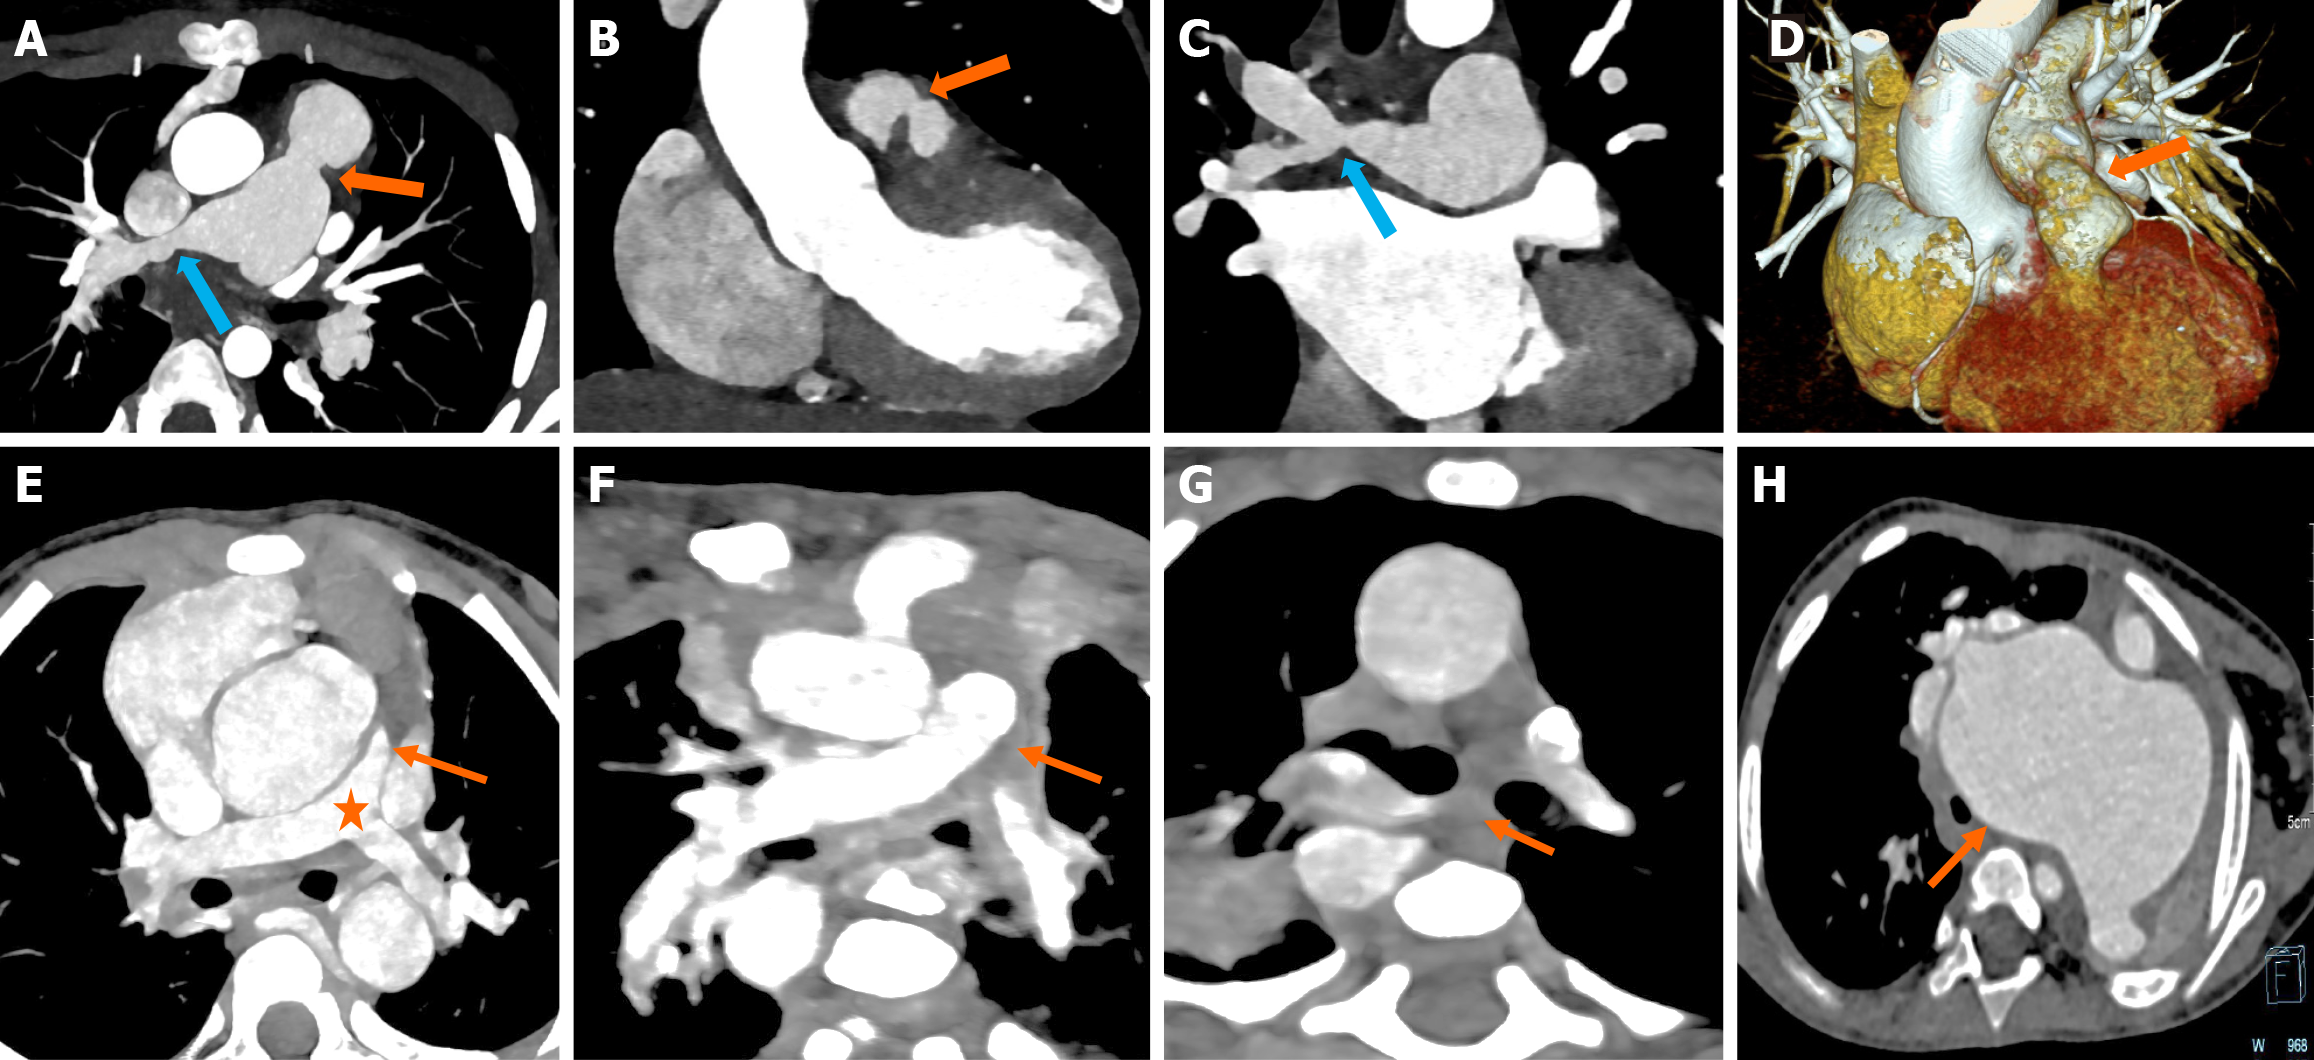

The classical components of TOF, including perimembranous VSD, aortic override, pulmonary stenosis/atresia, and consequent right RVH, are very well delineated on CT (Figure 5A-C). The aortic override in TOF is typically less than or equal to 50%, in TOF. The degree of RVOTO is variable. Pulmonary stenosis may be infundibular, valvular, or supravalvular. Isolated left PA stenosis is the most common (Figure 5D-F). Rarely, stenosis of the branch PA may be coexistent with main PA stenosis (Figure 6A-D)[37]. In cases with pulmonary atresia, the main PA is atretic, and the branch pulmonary arteries may be confluent or isolated (Figure 6E-G). The PV may be absent in 3%-6% cases and is characterized by an aneurysmal main PA (Figure 6H)[38].

Figure 5

Figure 5 Computed tomography images. A-C: Axial (A and B) and sagittal reformatted images (C) of computed tomography angiography in a child with cyanosis, showing infundibular pulmonary stenosis (block arrow in A), right ventricular hypertrophy (asterisk in B), perimembranous ventricular septal defect (block arrow in B) with 50% aortic override (asterisk in C) consistent with classical tetralogy of Fallot; D-F: Axial (D and E) images showing stenosis at the origin of the left pulmonary artery (arrow). The right pulmonary artery was normal (asterisk); F: Three-dimensional volume rendered image showing the left pulmonary artery stenosis (arrow).

Figure 6

Figure 6 Computed tomography images. A-D: Oblique axial maximum intensity projection images and volume rendered image showing supravalvular main pulmonary artery (orange arrow) and right pulmonary artery (blue arrow) stenosis in a known case of TOF (A); coronal reformat image showing the main pulmonary artery stenosis (arrow) (B); coronal reformat image showing right pulmonary artery stenosis (blue arrow) (C); three-dimensional volume rendered image showing supravalvular main pulmonary artery stenosis (arrow) (D); E-H: Axial computed tomography angiography images showing pulmonary arterial anomalies in different patients of tetralogy of Fallot. E: Pulmonary atresia (block arrow) with reformed, confluent pulmonary arteries (asterisk); F: Pulmonary atresia with non-confluent, reformed pulmonary arteries (block arrow); G: Pulmonary atresia with absent main and branch pulmonary arteries (block arrow); H: Aneurysmal dilatation of the main pulmonary artery (block arrow) due to absent pulmonary valve.